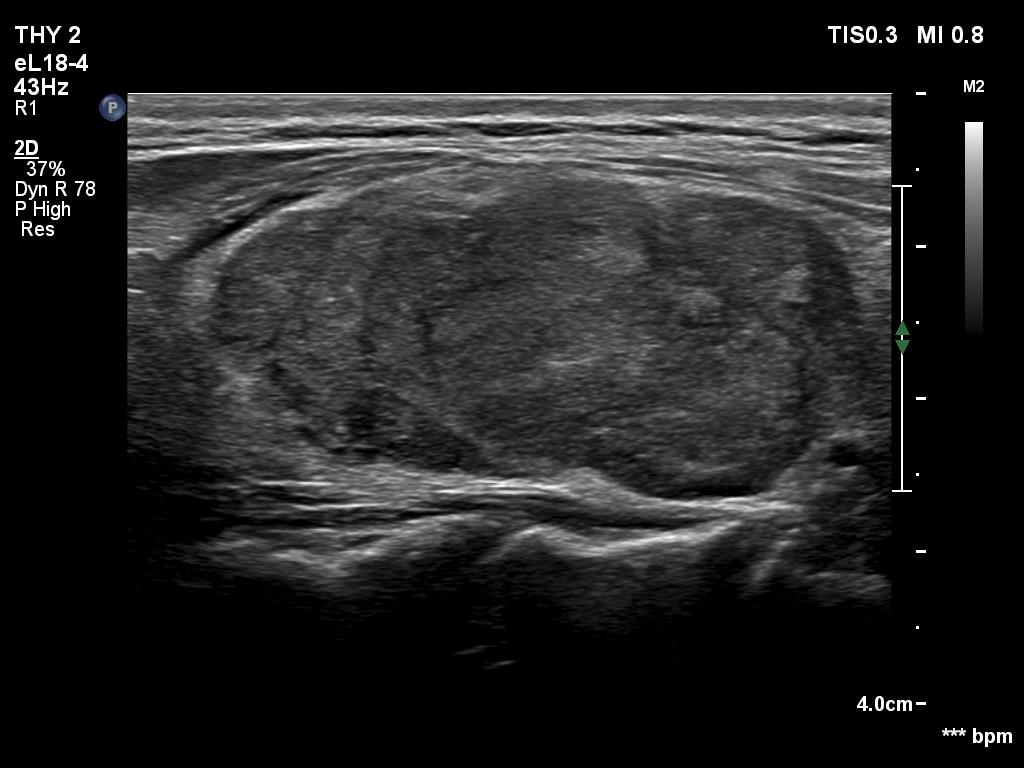

The operated thyroid - case 1570 (ultrasonographic picture 3)

Left lobe, longitudinal scan. The operated left lobe is composed of a central hypoechoic mass surrounded with thin echonormal tissue. The former has irregular, lobulated margins. This is a typical presentation of an operated, resected lobe frequently misinterpreted as a hypoechoic nodule.